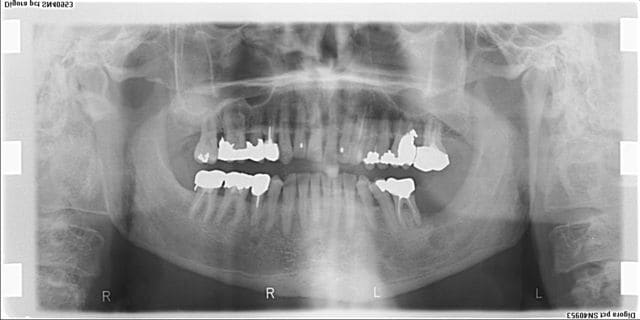

La pano....

...la voilà.

Il n'y aurait pas une lésion osseuse juste sous ces bourgeons???

Ca fait quand meme pas très bénin, non?

J'ai vu une fois un carcinome verruqueux qui avait cet aspect exterieur et le meme aspect radio.

dis donc c'est vilain mon steph, c'est surement pas le moment mais tous le groupe molaire de ce coté, haut est bas serait mieux ailleurs qu'en bouche